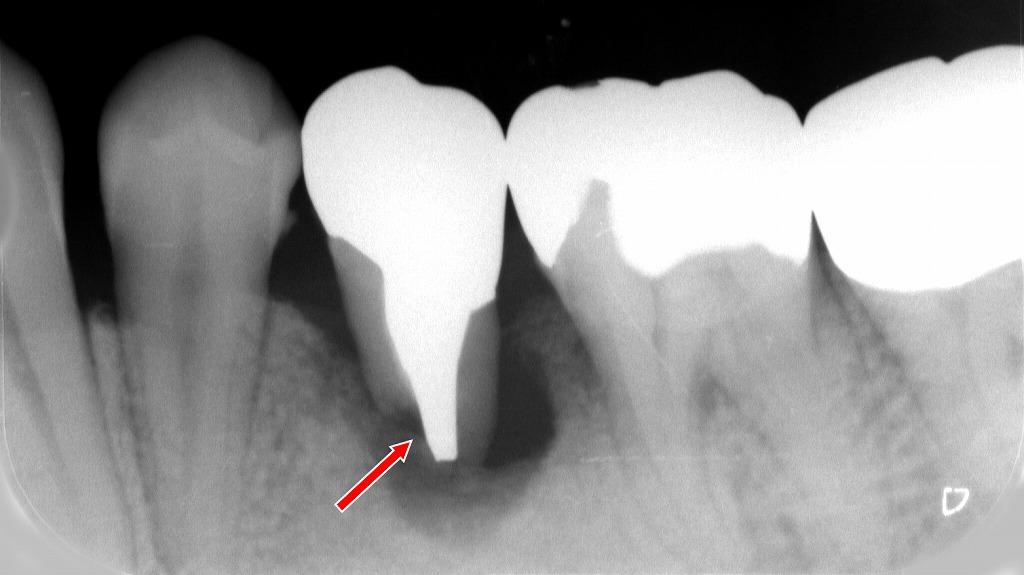

➤ 下顎5番・下顎6番(永久歯)が異常に歯根吸収を起こしている状態

- 本来吸収しないはずの永久歯の歯根が部分的に溶けている。

- 矢印部に見られるように、

**歯根の外側に境界の不明瞭な吸収像(くぼみ)**が確認できる。 - 生理的吸収と異なり、局所的・不規則な形を示すのが特徴。

- 原因としては以下が多い:

- 根尖性歯周炎(根の先の炎症)

- 外傷

- 矯正力の過剰

- 歯根破折

- 嚢胞や腫瘍の圧迫

● 意味

- 自然には止まらない進行性の吸収。

- 多くの場合は治療介入(根管治療、原因除去)が必要。